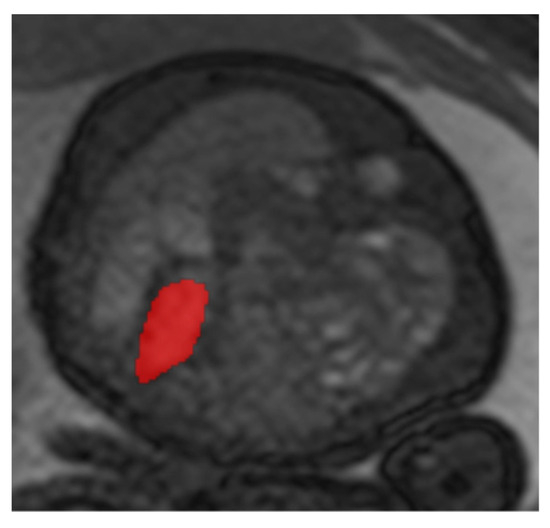

2.4. Percentage Area of Left Ventricle (pALV)

The measurement procedure was analogous to the determination of the mediastinal shift angle (MSA) using T2-weighted sequences. For the determination of the cardiac parameter “percentage Area of Left Ventricle” (pALV), which represents the percentage area of the left ventricle, the absolute areas of both inner ventricular surfaces of the heart are first measured in their greatest extent in the four-chamber view on a transverse sectional plane in relation to the fetus (Figure 2). For this purpose, the inner surfaces of the right and left ventricles were segmented, and the surface was automatically calculated by postprocessing.

This figure illustrates a T2 steady-state free-precision (TRUFI) sequence in the axial slice plane (uniform four-chamber plane) of a fetal MRI scan in a patient with left congenital diaphragmatic hernia (CDH). This MRI representation shows an example of the segmentation of the right inner ventricular surface (red surface in the figure).